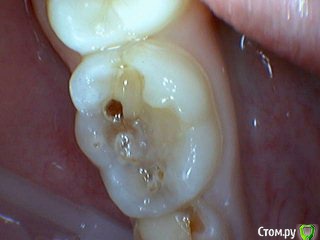

Давлетшин Опубликовано 15 мая, 2017 Поделиться Опубликовано 15 мая, 2017 (изменено) Есть такое слово НАДО. И надо делать ОПТГ в 6-7 лет. Здесь должна быть работа с рентгенологом. Можно отправлять снова и снова на снимки., пока не научится делать, с первого раза. Пусть рентгенолог объяснит позицию " чтобы не облучать". только цифрами и норм. актами. ну а потом и расстрелять можно, только не вы расстреливайте, а родители, за работу спрос с ВАС, а как вы можете сделать качественную диагностику и лечение без снимков. Вообще мне кажется на форуме, надо как то писать, когда задается вопрос, кто в каких условиях работает. может и более правильные рекомендации давали бы. Я дам одну рекомендацию. После 6-7 лет всех на ОПТГ. хоть за 100 км. через 15-20 ОПТГ пойдут"неожиданности" и еще больше укрепитесь в нужности исследования. На десерт неожиданность. Причем подозрение как то интуитивно вышло. Коментировать фото "какой я хороший/плохой, почему без кофера?" не буду. Скажу что был индикатор. И по вашему профилю ВЫ из Молдовы. интересно на одном ли языке мы говорим? Я про молочные премоляры. Мы в России то по разному думаем хотя программа в институтах одинаковая. Изменено 15 мая, 2017 пользователем Давлетшин 1 Ссылка на комментарий